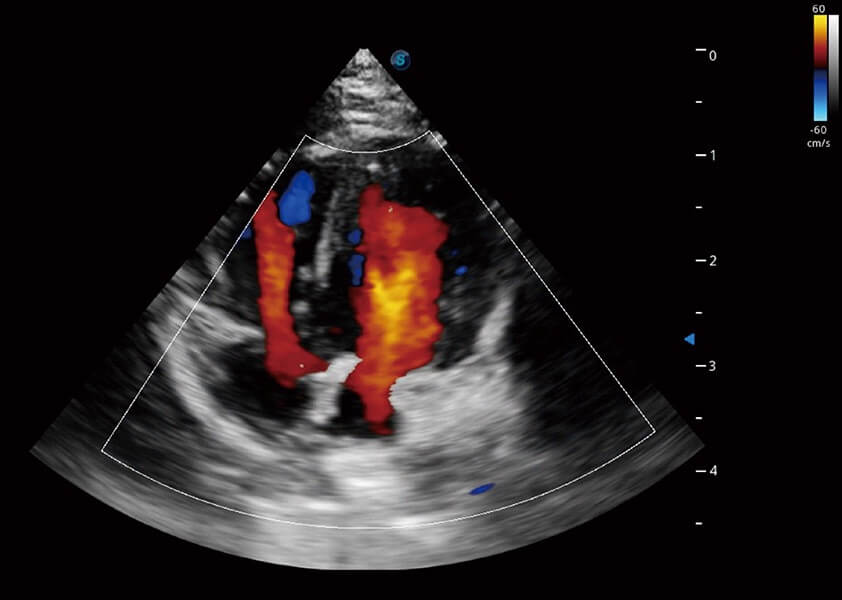

ProPet 60 作为一款高端台式动物超声设备,为动物医生的日常诊断提供了一系列贴合动物临床需求、解决临床实际问题的高级成像功能。凭借全系列高清探头,满足医生对腹部、心脏、生殖、浅表、肌骨等成像的所有需求,切实帮助您提升检查效率,提高诊断信心。

动物是人类最亲密的朋友和最值得信赖的伙伴。哈哈体育官网也一直致力于探索动物专用的超声影像解决方案。 全新推出的ProPet系列,是哈哈体育官网在动物超声影像智能化、专业化、精准化的一次跨越式革新。动物不能用言语来表述自己的不适,通过超声影像,ProPet系列搭建了动物医生与不同物种沟通的“桥梁”,为动物医生注入了“治愈之力”。